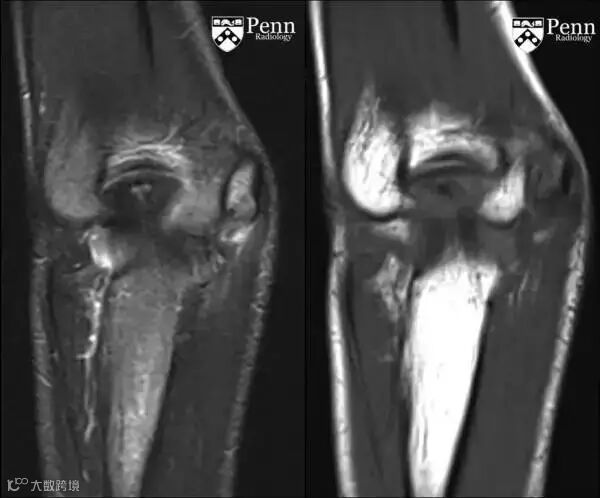

MRI:肱骨内上髁可见长T1长T2信号,骨骺板增宽。

3.病史和体格检查对诊断很关键,损伤的时间和机理,疼痛的部位、症状为诊断的关键因素。平片上肱骨内上髁炎表现为一系列征象:肱骨内上髁透亮线、分离或硬化,骨骺板增宽。MRI肱骨内上髁可见长T1长T2信号影,骨骺板增宽,有时同时可见屈肌总腱的T2信号增高。